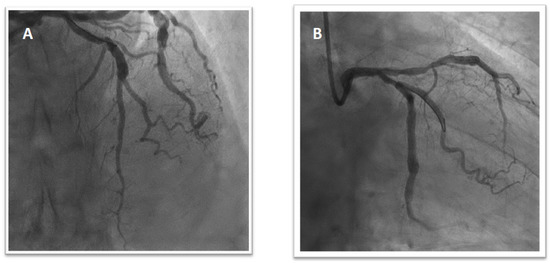

1.1. Patient 1

1.2. Patient 2

1.3. Patient 3

1.4. Patient 4

1.5. Patient 5